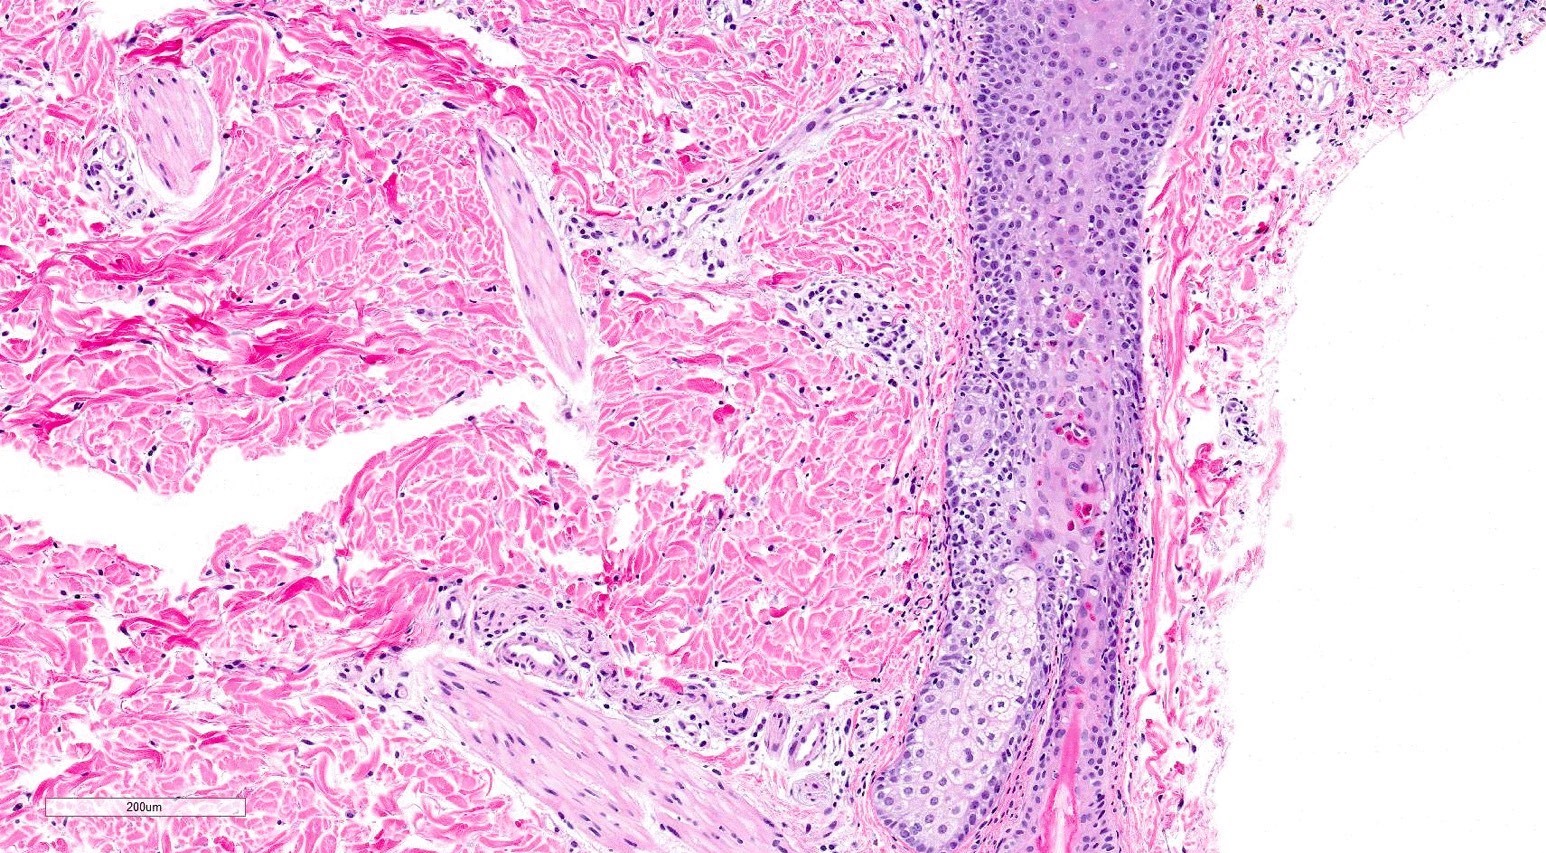

Microscopic (histologic) description

- Chronic sclerodermoid GVHD

- Dermal sclerosis (thickened compact collagen with loss of periadnexal fat)

- Manifests with localized morphea-like features, diffuse sclerosis or lichen sclerosus-like features

- Localized morphea-like features and diffuse sclerosis are largely confined to the reticular dermis or subcutaneous septa with little or no epidermal involvement

- Lichen sclerosus-like GVHD: collagen alteration is confined to the papillary dermis (hyalinzation of the papillary dermis), often with residual interface changes characterized by the presence of mild vacuolar alteration, melanophages and sparse superficial perivascular lymphocytic infiltrate

- In the fasciitis variant, biopsy specimens show only fibrous thickening of the fascia with adjacent inflammation without epidermal or dermal involvement

Microscopic (histologic) images

Contributed by Silvija P. Gottesman, M.D. and Ohoud Aljarbou, M.D.